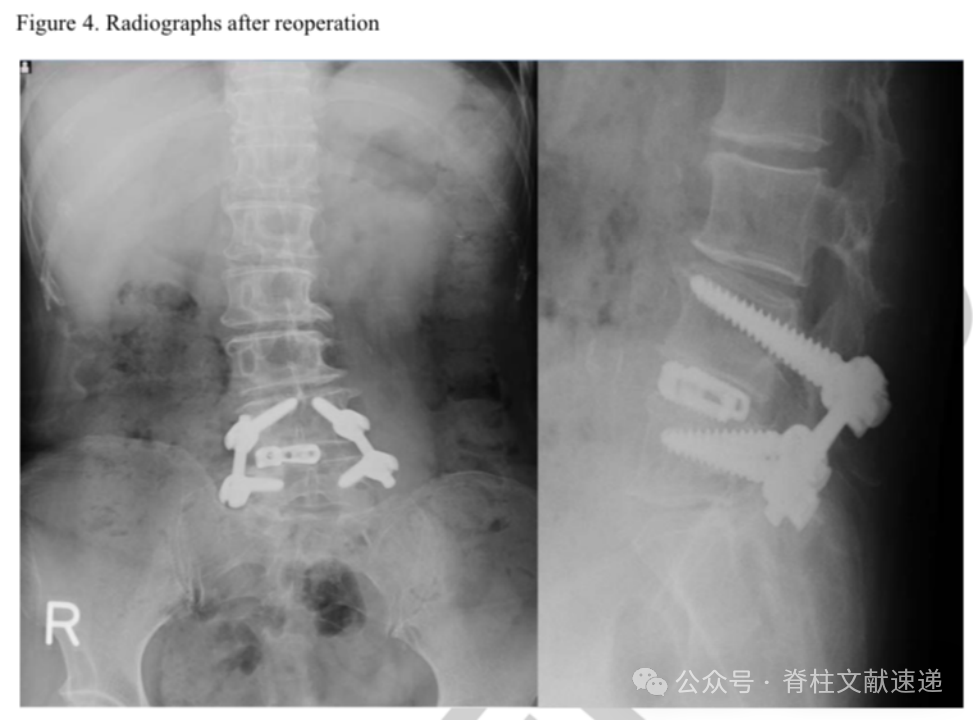

文中病例:69岁女性,右下肢放射性疼痛。存在脊柱侧弯,髓核摘除术后2月进行了融合手术。